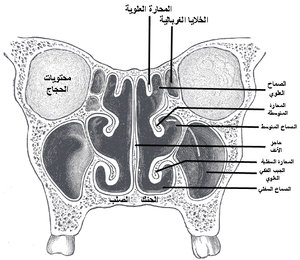

الجدار الوحشي

يعتبر الجدار الوحشي أكثر جدران جوف الأنف تعقيداً؛ إذ يساهم في تركيبه كل من العظم الأنفي والغربالي والدمعي والفكي العلوي والصفيحة العمودية للعظم الحنكي والصفيحة الجناحية الأنسية للعظم الوتدي. يتميز الجدار الوحشي ببروز ثلاث تراكيب عظمية تتوضع فوق بعضها تدعى المحارات الأنفية.[1][6] كما يتميز الجدار الوحشي بوجود ارتفاع دائري ينتج عن بروز الخلايا الغربالية المتوسطة نحو الأنسي يدعى الفقاعة الغربالية، وإلى الأسفل والأمام من هذه الفقاعة يوجد ثلم متقوس يدعى الفرجة الهلالية.[6]

التقسيم التشريحي

يقسم جوف الأنف بواسطة حاجز الأنف إلى قسمين أيمن وأيسر، ويقسم كل منهما بواسطة المحارات الأنفية الثلاثة إلى أربع فسحات هي من الأعلى للأسفل:

- الردب الوتدي الغربالي: يقع فوق المحارة الأنفية العلوية وخلفها.

- الصماخ الأنفي العلوي: يقع تحت المحارة العلوية ووحشيها.

- الصماخ الأنفي الأوسط: يقع تحت المحارة الأنفية الوسطى ووحشيها.

- الصماخ الأنفي السفلي: يقع تحت المحارة الأنفية السفلية ووحشيها.[1]

الاتصالات

يتصل جوف الأنف مع الوسط الخارجي في الأمام عبر المنخر ويتصل مع البلعوم الأنفي في الخلف عبر فتحة بيضية الشكل تدعى المنعر. كما يتصل جوف الأنف مع الجيوب جانب الأنفية عبر فتحات خاصة، ويسمح وجود هذه الفتحات بتفريغ محتويات الجيوب ومنع تراكمها. تفتح القناة الأنفية الدمعية التي تنقل الدمع على الصماخ الأنفي السفلي.[1][6][8] يفتح على جوف الأنف في الجمجمة الجافة (أي بعد إزالة المخطيات) بالإضافة لما سبق كل من الثقبة الوتدية الحنكية والنفق القاطعي والصفيحة المصفوية.[1]